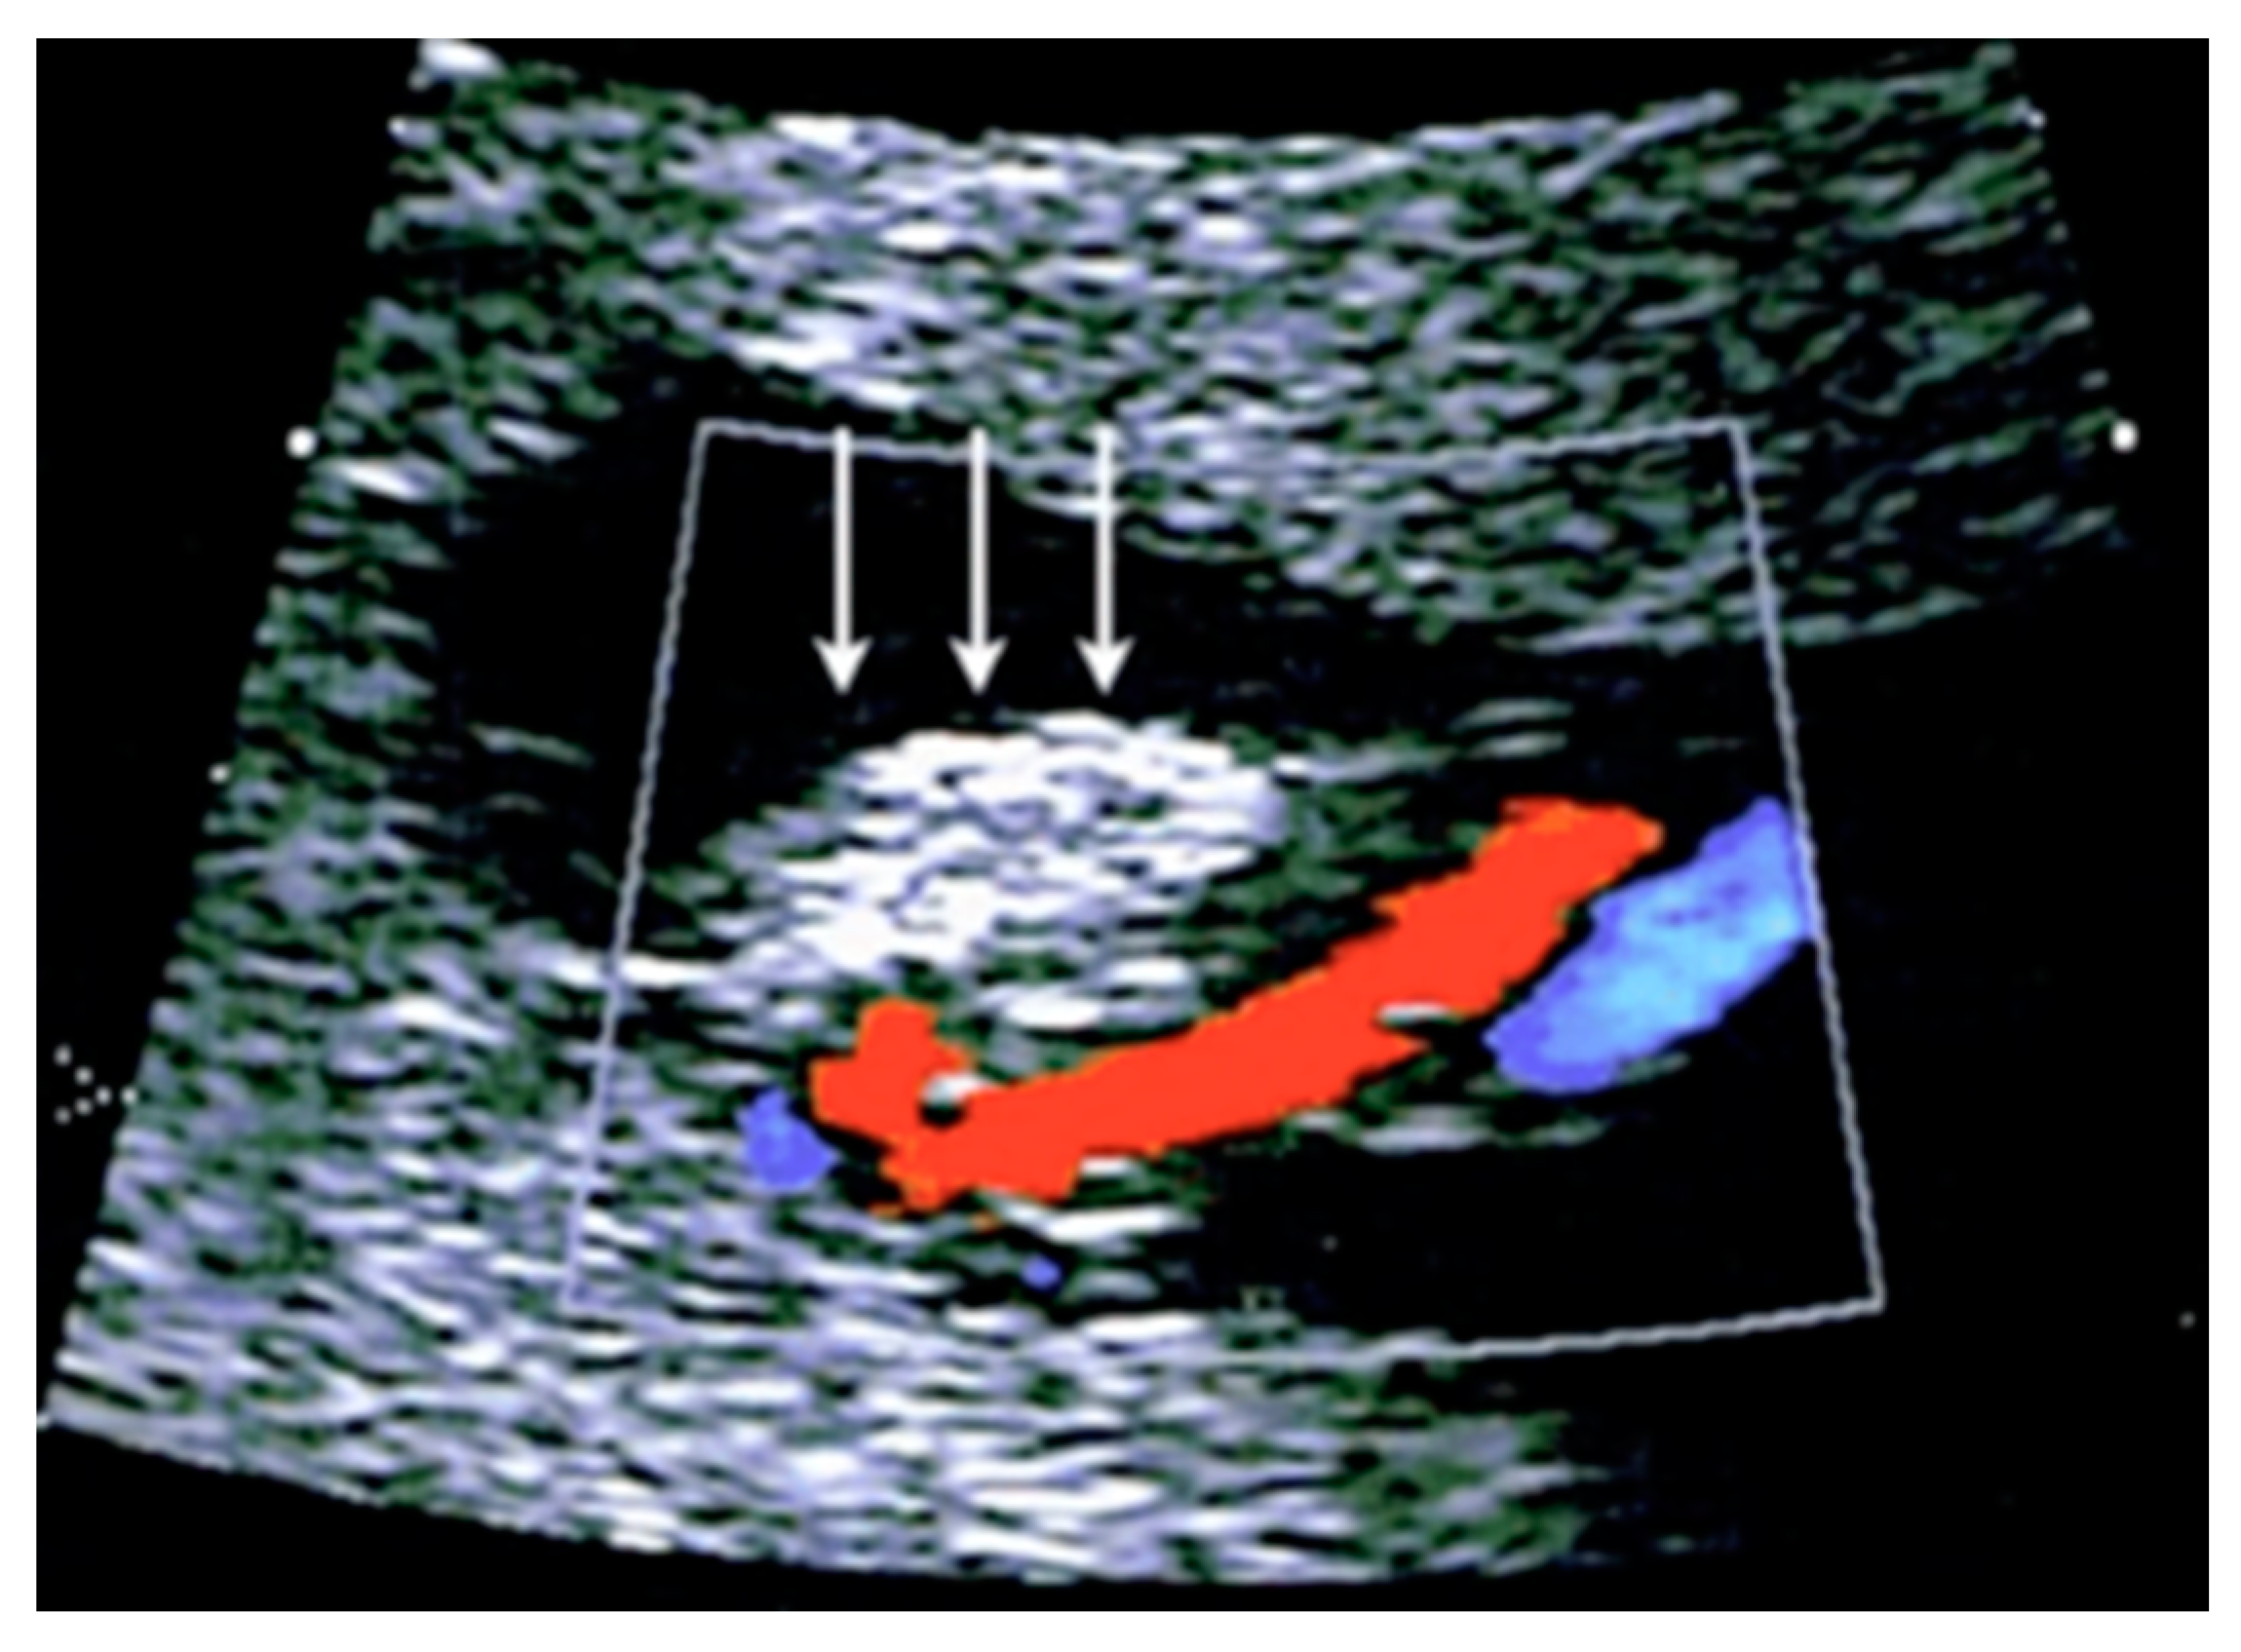

3.2.7. Umbilical Cord Hemangioma

3.2.8. Umbilical Cord Hematoma